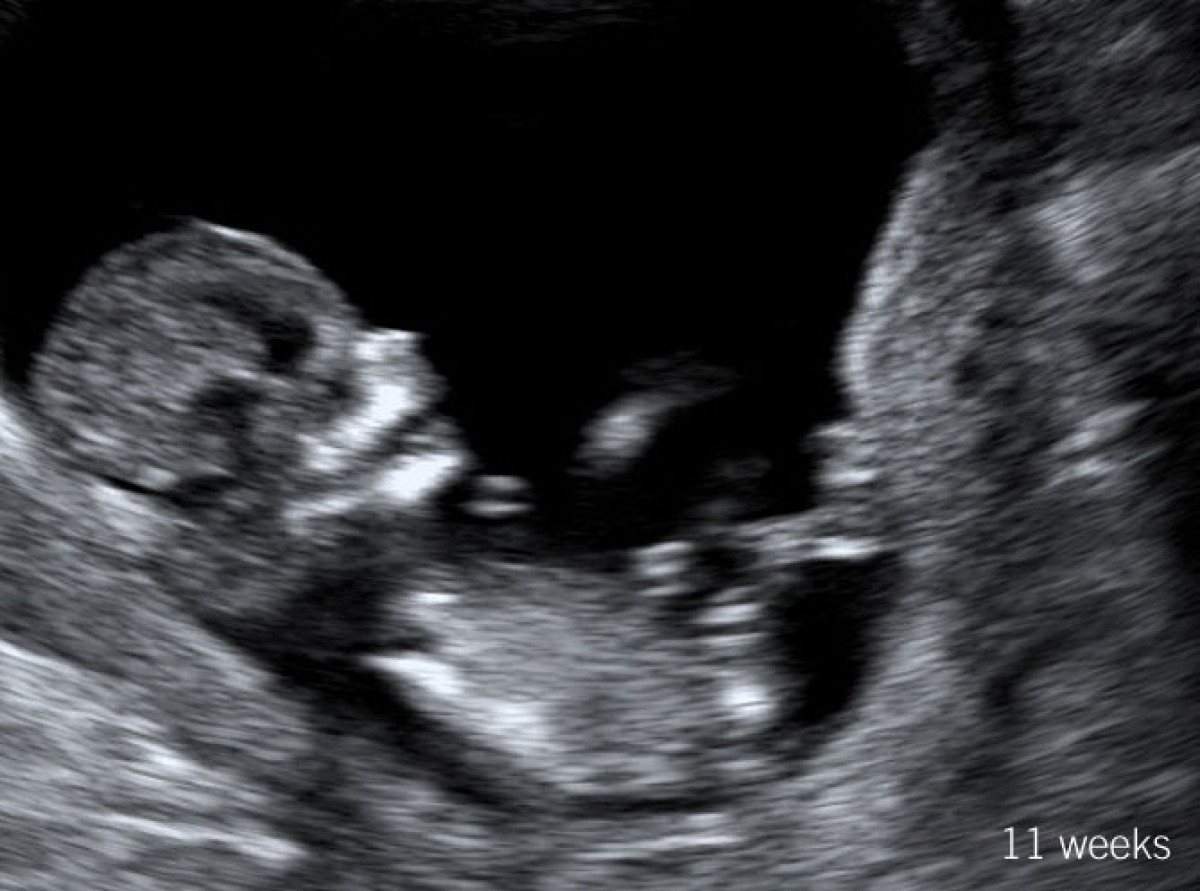

Sam & Norah

11 weeks